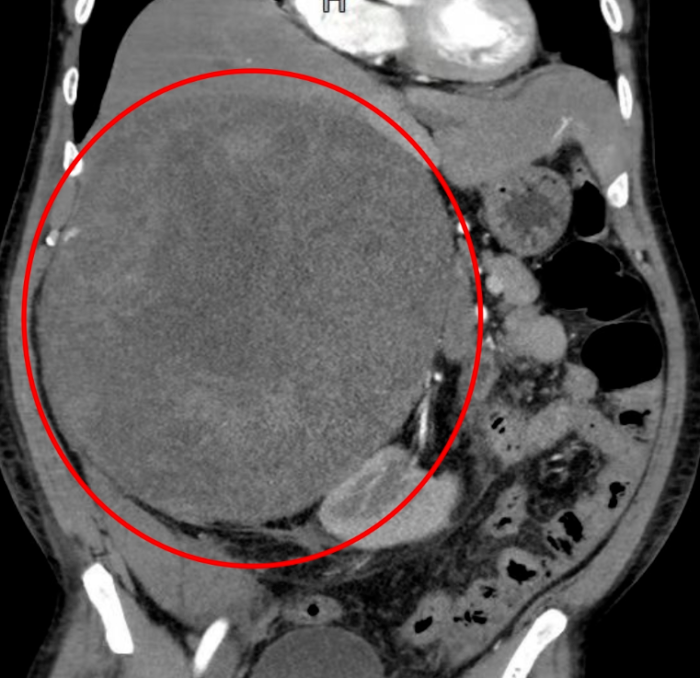

术前CT影像,红圈处为肿瘤。

7月2日,贵医附院泌尿外科顾昌世主任团队凭借深厚的解剖功底和丰富的手术经验,向这颗“定时炸弹”发起“进攻”。尽管泌尿外科医生处理腹膜后肿瘤司空见惯,但真正打开患者腹腔的时候还是让他们震惊了,这个肿瘤长径达22cm,巨大的肿瘤与腹腔脏器粘连严重,且周边大血管环绕,剥离难度远超常规预期,这给手术团队带来了巨大挑战。